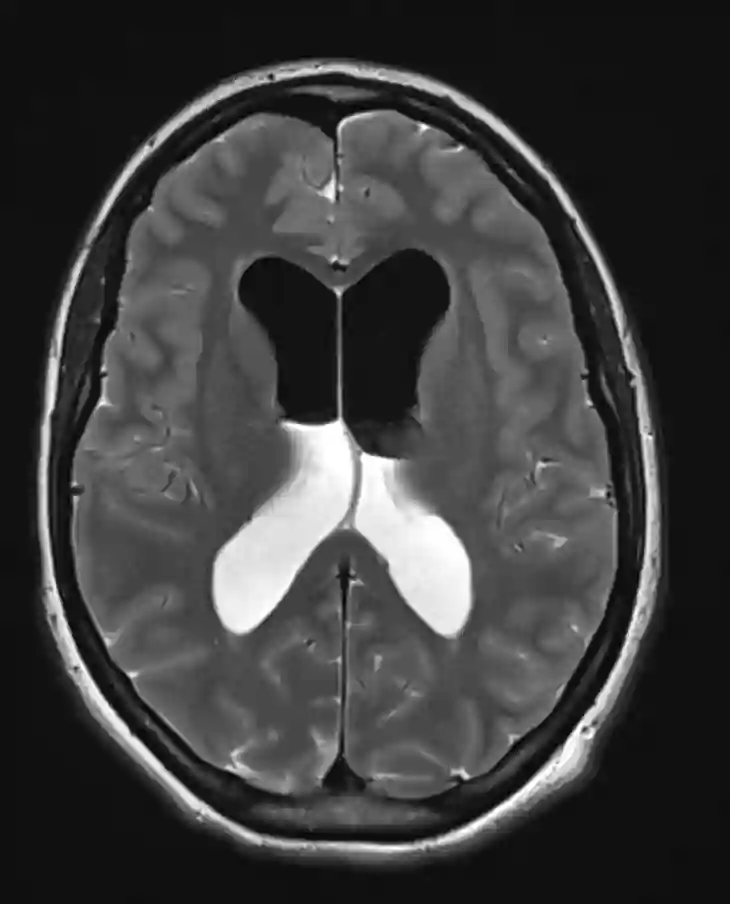

Die intrakraniellen Lufteinschlüsse lassen sich optimal in einer CT-Bildgebung als auch in einer MRT Bildgebung darstellen. Ein ausgeprägtes Pneumocephalus mit Kompression des Frontallappens kann sich in der CT-Bildgebung als sogenanntes Mount Fuji Zeichen darstellen.

MRT